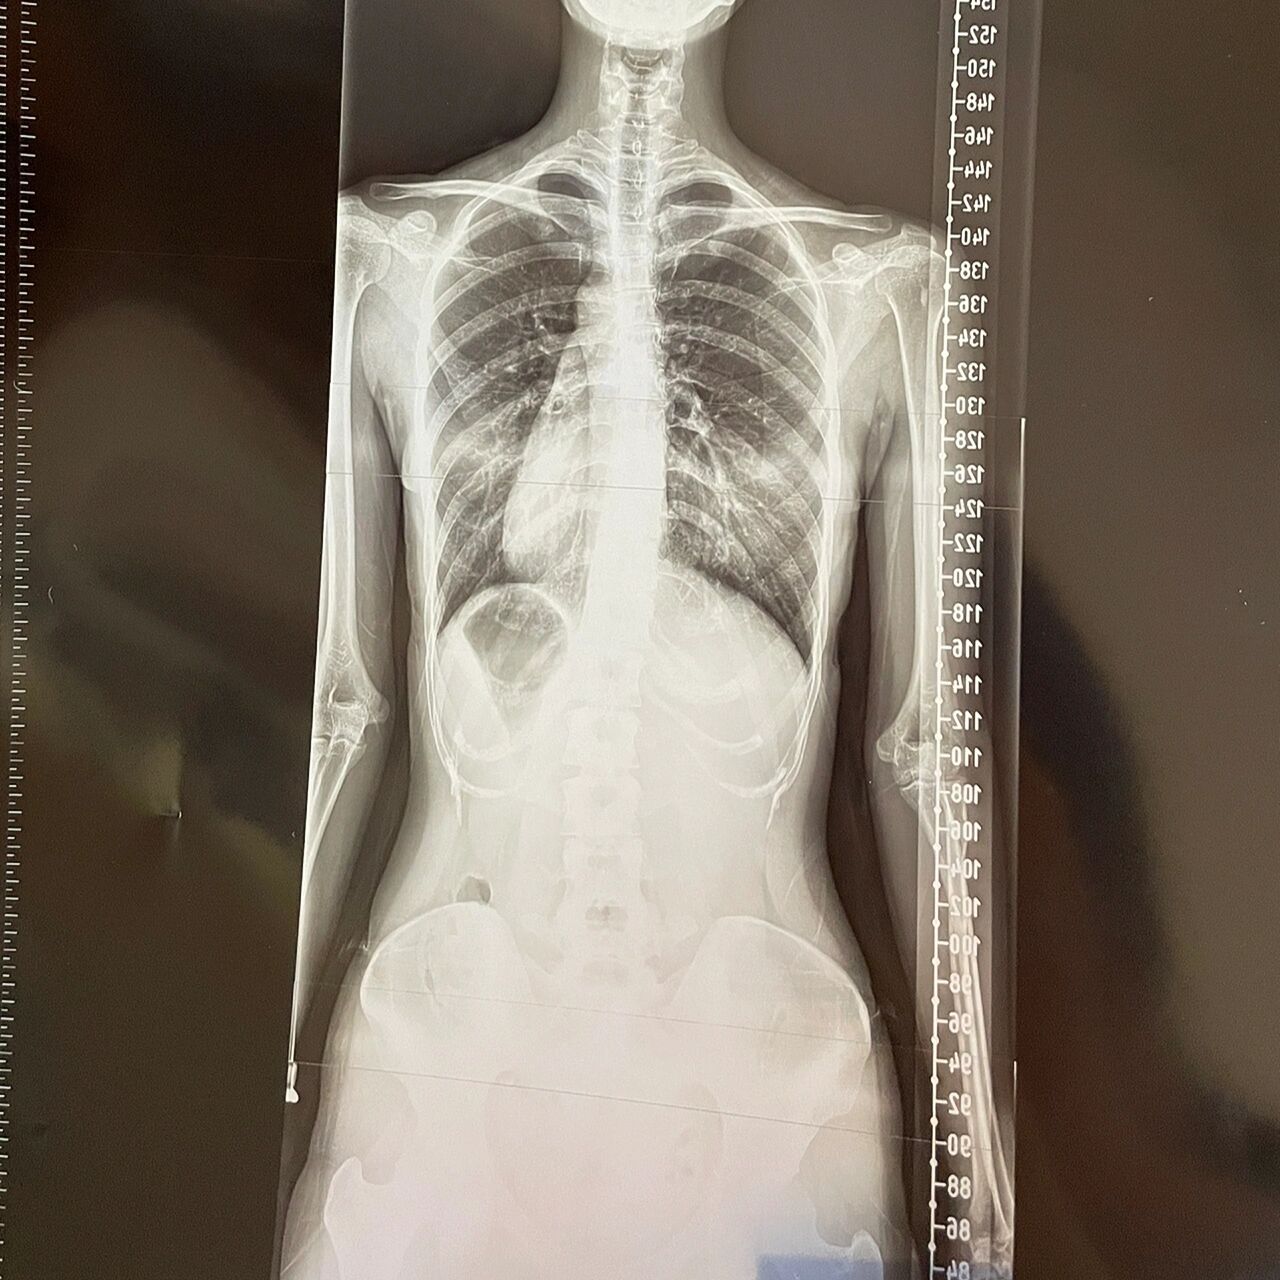

脊柱侧弯 腰线不对称,走路走久了腰会很疼,坐久了会背疼 以下补充